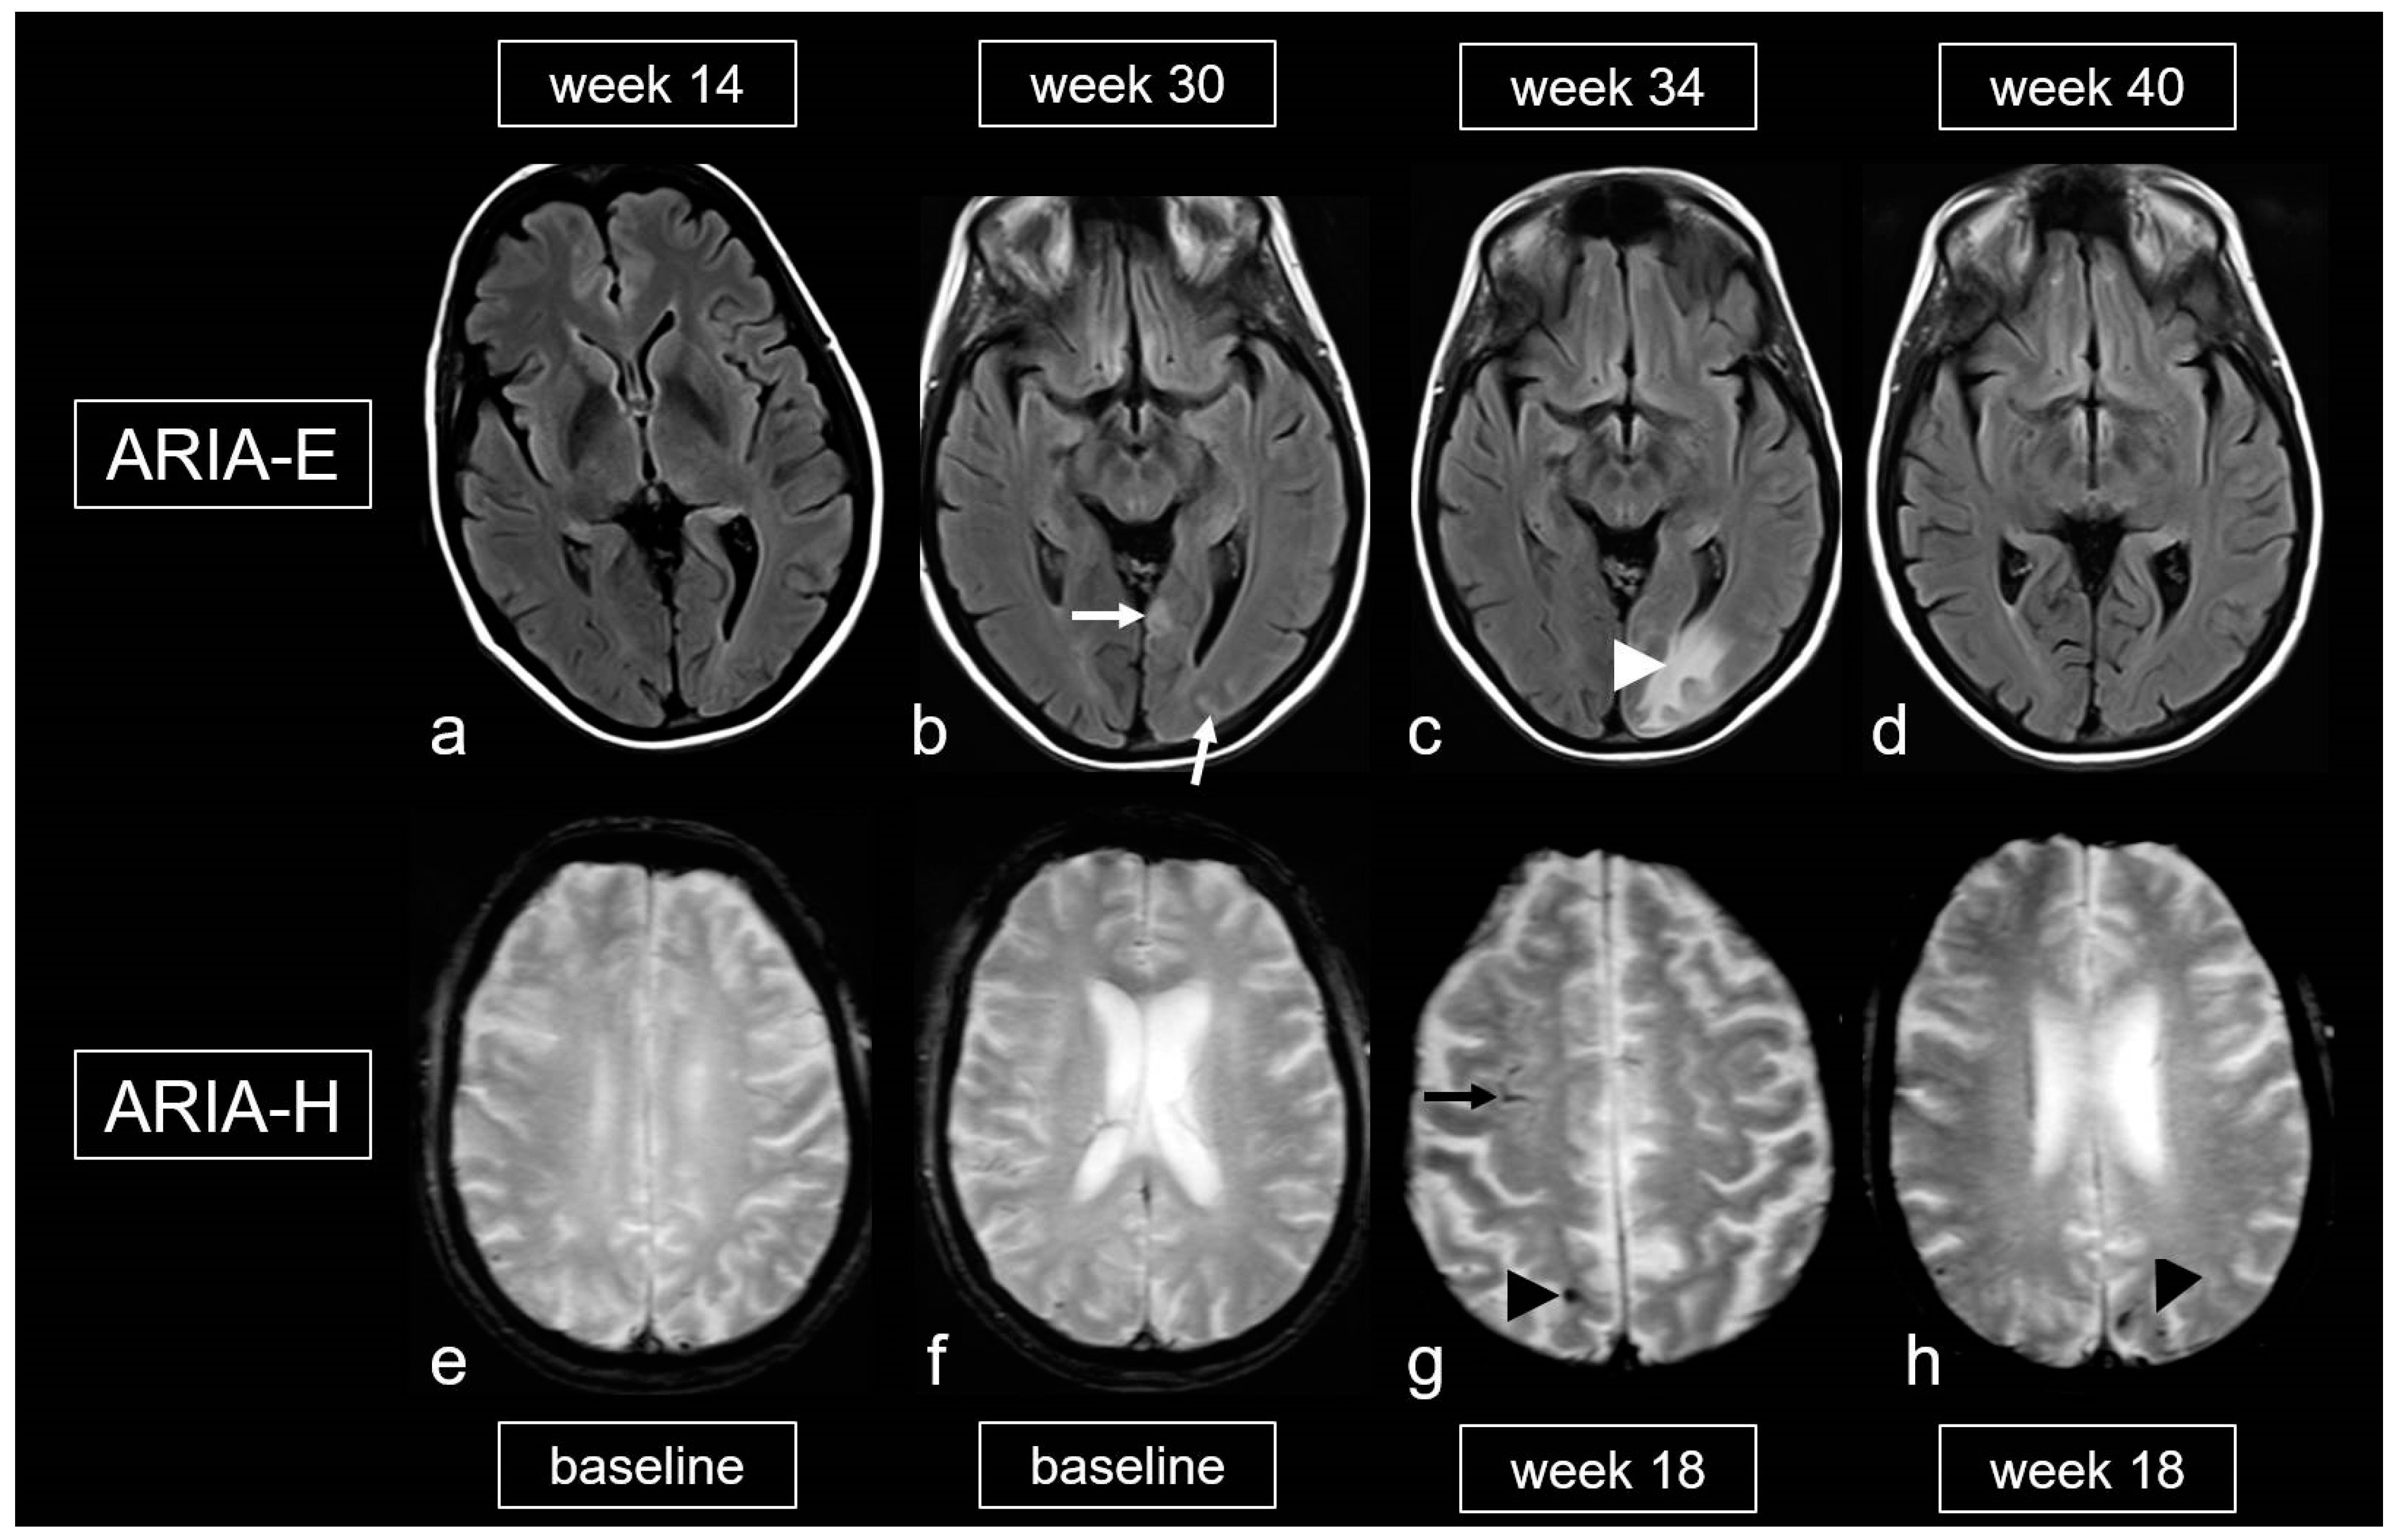

CAA-related inflammation (CAA-ri) is a subtype of CAA characterized by the presence of autoantibodies against Aß in the arterial vessel walls [95,96,97,98,99,100]. The inflammation, which affects both the vascular and perivascular regions, leads to vasogenic edema and leptomeningeal effusions, resulting in hyperintense signal changes on T2-weighted sequences [96,100]. These MRI features are identical to the imaging changes observed during amyloid antibody therapy [97,101,102], in which these are known as “amyloid related imaging abnormalities” (ARIA) (Figure 6) [101,102,103,104,105]. ARIA-E (edema, effusion), characterized by circumscribed peripheral edema often involving the cortex [101,106,107], is frequently accompanied by MBs, cSAH or cSS (ARIA-H, hemorrhagic) resulting in overall picture that aligns with CAA-ri, making both entities morphologically indistinguishable [101,103,104,105].

Figure 9.

Amyloid-related imaging abnormalities (ARIA). (a–d): Fluid-attenuated inversion recovery (FLAIR) images showing ARIA-E (edema, effusion) in a patient treated with aducanumab, week 14 (a), 30 (b), 34 (c) and 40 (d) after treatment initiation; sulcal effusions ((b), arrow) and edema in the occipital lobe ((c), arrowhead), completely decreased at week 40 (d). (e–h): T2*-weighted images (WI) demonstrating ARIA-H (hemorrhagic) in a 68-year-old woman treated with aducanumab, baseline (e,f) and week 18. (g,h): Cortical superficial siderosis (cSS; arrow) and microbleeds (MB; arrowhead); MRI 1.5T.

Finally, the literature also mentions an iatrogenic variant of CAA-ri related to the frequent and dose-dependent occurrence of ARIA, which affects up to 41.3% [101,105,124,125]. The gradations of ARIA-E and ARIA-H are outlined in Table 5 and Table 6 [105,126]. It is important to note that, unlike spontaneous CAA-ri, only about 20% of patients with proven ARIA on MRI exhibit clinical symptoms, such as headache, confusion and other psychopathological abnormalities, visual disturbances, nausea and vomiting [101,105,124,125,126]. These symptoms typically arise within the first 3 months of treatment and are usually reversible.